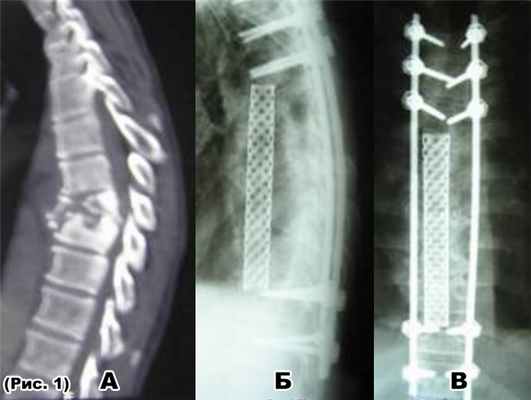

а) тотальная деструкция Th6- Th7-Th8 (туб. спондилитTh6- Th7-Th8);

б) удаление телTh6-Th7-Th8 позвонков боковой спондилодез мешем с ауторебром;

В) транспедикулярнаяфиксацияTh3- Th4-Th5-Th10- Th11 позвонков.

в) транспедикулярнаяфиксацияTh5-Th6- Th11- Th12 позвонков.